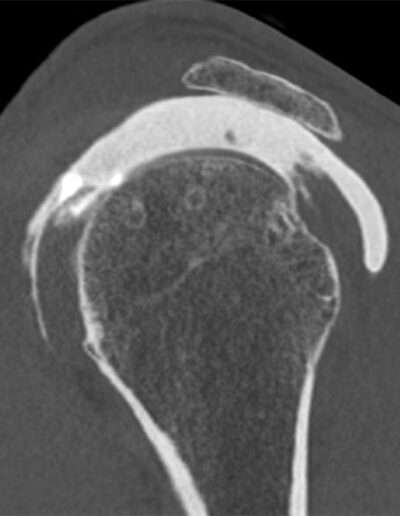

Shoulder Right

Patient 76 y/o, Male, right-handed

• 03/2021: Supraspinatus + Infraspinatus double-row repair (Dr. Laurent LAFOSSE)

• 06/2021: Revision SSP+ISP double-row repair (Dr. Laurent LAFOSSE)

• 12/2024: Pain and weakness in ER2